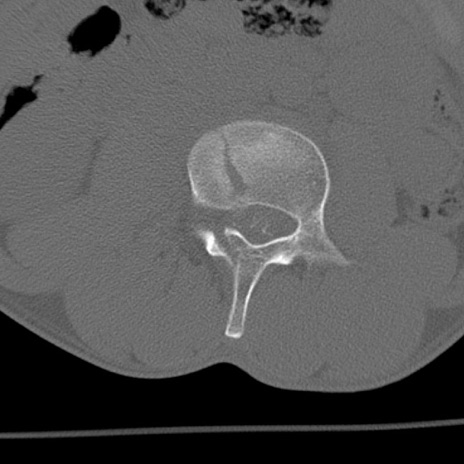

症例3 腰椎CT(横断像)

腰椎CT